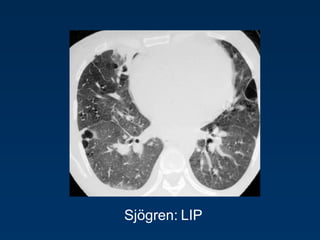

LIP

= Lymphocytic Interstitial Pneumonia

Sjögren: LIP

Rarely idiopathic

In association with:

Sjögren‟s syndrome

Immune deficiency syndromes, AIDS

Primary biliary cirrhosis

Multicentric Castlemean‟s disease

Sjoegren disease

Dry eye and dry mouth

Fibrosis, bronchitis and bronchiolitis

Overlap

Sarcoid, DM/PM, MXCT

SLE, RA (pleural effusion)

Up to 40 x increased risk for lymphoma (mediastinal

adenopathy) and

2 x times increased risk for neoplasma